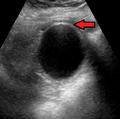

Acute cholecysitis as seen on ultrasound. Closed arrow points to gall bladder wall thickening. Open arrow points to stones in the GB